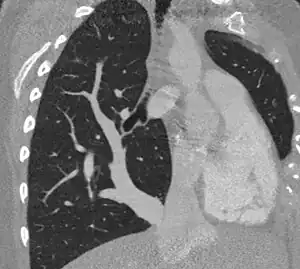

| Scimitar syndrome chest CT | |

Scimitar syndrome, or congenital pulmonary venolobar syndrome, is a rare congenital heart defect characterized by anomalous venous return from the right lung (to the systemic venous drainage, rather than directly to the left atrium).[1] This anomalous pulmonary venous return can be either partial (PAPVR) or total (TAPVR). The syndrome associated with PAPVR is more commonly known as Scimitar syndrome after the curvilinear pattern created on a chest radiograph by the pulmonary veins that drain to the inferior vena cava.[2] This radiographic density often has the shape of a scimitar, a type of curved sword.[2] The syndrome was first described by Catherine Neill in 1960.[3]

The anomalous venous return forms a curved shadow on chest x-ray such that it resembles a scimitar. This is called the Scimitar Sign. Associated abnormalities include right lung hypoplasia with associated dextroposition of the heart, pulmonary artery hypoplasia and pulmonary sequestration. Incidence is around 1 per 100,000 births.[4]

The diagnosis is made by transthoracic or transesophageal echocardiography and selective pulmonary angiography.[6] More recently by CT angiography or MR Angiography.

Pulmonary angiography demonstrates anomalous arterial supply to right lower lobe.[6]